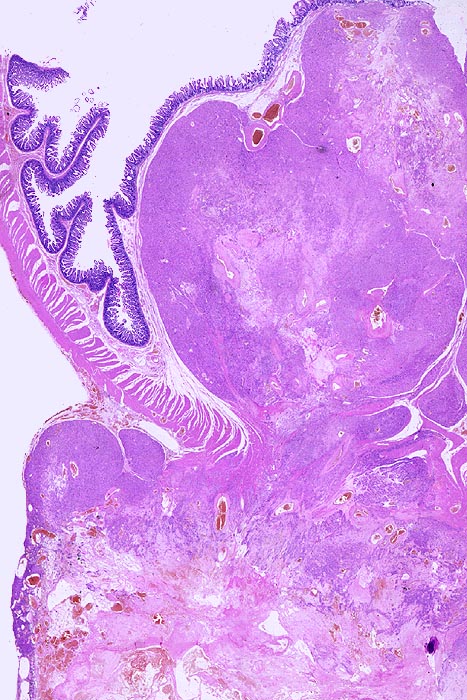

Gastrointestinaler Stromatumor (GIST)

benigner Tumor

Dünndarm

Teils zystischer von der Submukosa ausgehender scharf begrenzter Tumor mit Infiltration bis in das subseröse Fettgewebe. Die Mukosa über dem Tumor ist intakt.

Tumordurchmesser 4.5cm. Aktin und CD 117 positiv. Morphologische Ähnlichkeiten mit einem Leiomyom mit degenerativen Veränderungen (Sklerosierung, Zystenbildung). Kaum Mitosen. Keine Nekrosen.

Kein extraintestinaler Tumor.